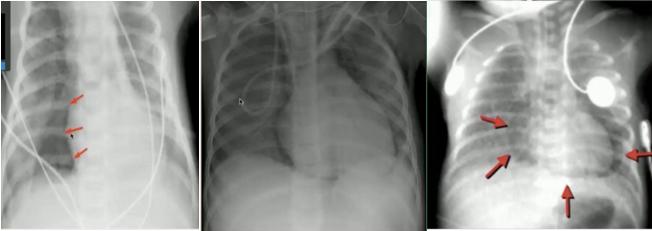

图9.肺实变(左)与肺不张(右)②细菌性与病毒性感染的鉴别

细菌性感染(支气管性肺炎):表现为沿着支气管分布的阴影;弥漫性毛绒状、边界不清,可延续到肺边缘;可伴有胸膜积液、空洞。

病毒性感染(间质性肺炎):表现为沿肺门分布的间质阴影;肺叶过度充气,表现为横膈膜变平;支气管增厚;可伴有分泌物阻塞导致局部不张。

图10.支气管性肺炎(左)与间质性肺炎(右)以下是细菌性感染的一些典型胸片:

图11.肺实变、大片阴影、肺量增加

图12.肺实变、胸腔积液

图13.球型实变(不应诊断为肿瘤/异物)

图14.“脊柱征”:位于心影后的下叶肺炎在正位片中不易看出,侧位片中可表现为椎体变白正常侧位片(左)与下叶肺炎(右)

以下是病毒性感染的一些典型胸片:

图15.沿肺门分布的线条状阴影,不累及胸膜边界

图16.正位片(左):肺不张(右上肺野肺裂上移);侧位片(右):过度充气(横隔变平)③支原体肺炎:可兼有细菌性及病毒性肺炎的表现,弥漫片状阴影或间质线性阴影,最常见表现为双下肺阴影伴积液,常伴有肺门淋巴结肿大。